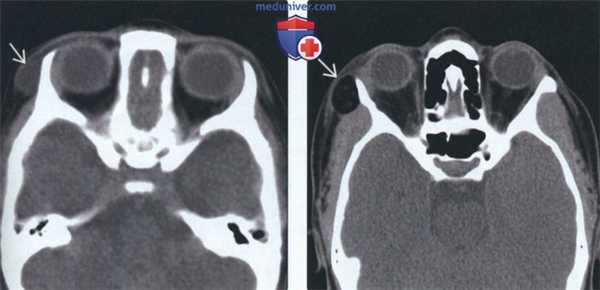

(Слева) На сагиттальной КТ (реконструкция) у десятилетнего ребенка с дермальным синусом носа определяется внутричерепное распространение дермоидной ки сты. Обратите внимание на кальцинат в области верхнего края дермоидной кисты.

(Справа) На сагиттальной томограмме (Т1 ВИ С+ FS) у ребенка в возрасте четырех дней с объемным образованием дна полости рта визуализируется патоморфологически подтвержденная многокамерная срединная дермоидная киста. В дифференциально-диагностический ряд нужно включать эпидермоидную кисту и лимфатическую мальформацию.

(Слева) На аксиальной КТ без КУ у четырехлетней девочки снаружи от латеральной стенки правой глазницы визуализируется ги поденсное объемное образование с четкими контурами без включений жира или кальцинатов; дифференциальная диагностика проводится между дермоидной и эпидермоидной кистой. При патоморфологическом иссле довании обнаружились придатки кожи, что позволило сделать заключение о дермоидной кисте.

(Справа) На аксиальной КТ без КУ у ребенка с длительной существующим пальпируемым объемным периорбитальным образованием визуализируется хорошо отграниченный дермоид, содержащий жир, сглаживающий наружную стенку глазницы.